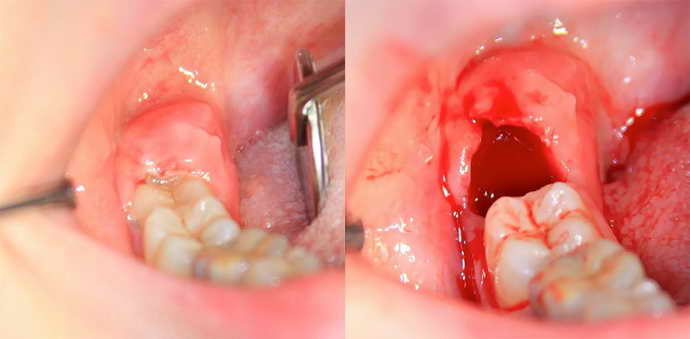

Тактика удаления зуба при флюсе определяется во время диагностики. Далее пациенту ставят обезболивающие уколы в необходимом количестве. Одна из методик удаления выглядит так:

- Стоматологическим прибором или лазером делают надрез на надкостнице.

- Получившуюся рану обрабатывают антисептиком, иссушают, подтверждают устранение всего гноя.

- Проводят осмотр поврежденных тканей, устраняют их, используя хирургические инструменты.

- Теперь приступают к удалению зуба – полностью, с нервом и корнем.

- В образовавшуюся лунку ставят дренаж и накладывают швы.

- Через некоторое время пациент приходит для снятия дренажа и устранения швов, финальный осмотр требует наложения рассасывающихся швов.

Очень важно соблюдать санитарные нормы, чтобы не допустить повторного заражения тканей или крови.